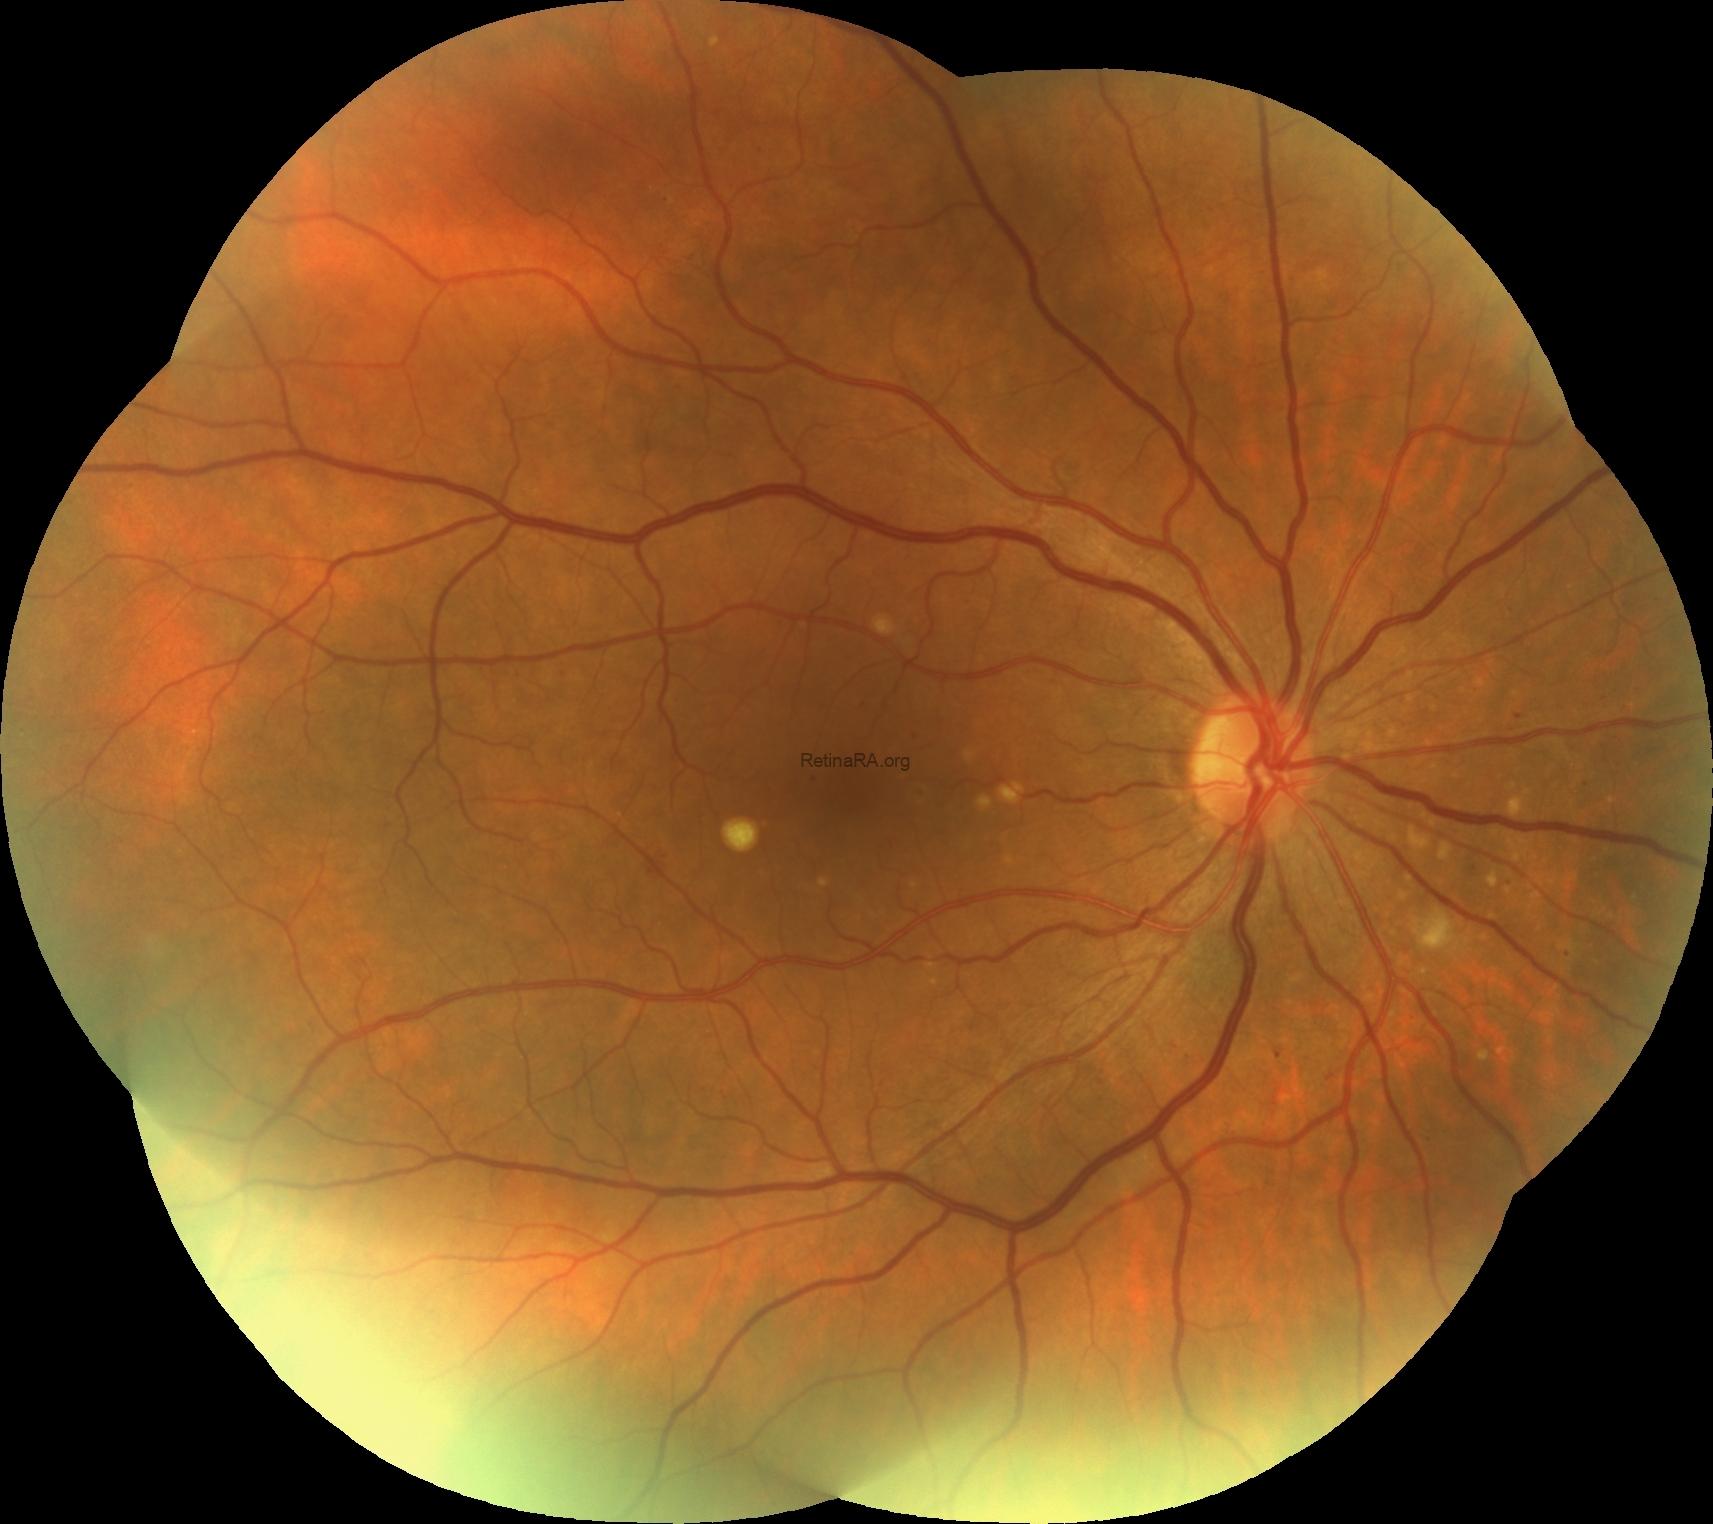

Fundus images of both eyes showed diabetic microaneurysms and a few yellow large drusen (

>125 μm) in the macula.